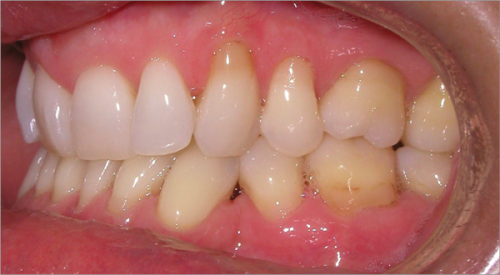

44 year old female:

Diagnosis:

- Upper and lower arch collapse due to missing teeth

- Retrusive angulation of upper & lower front teeth

- Severe collision and wear of front teeth

Treatment:

- Combination of Invisalign and braces

- Creating space for placement of an implant in the lower arch

- 28 months